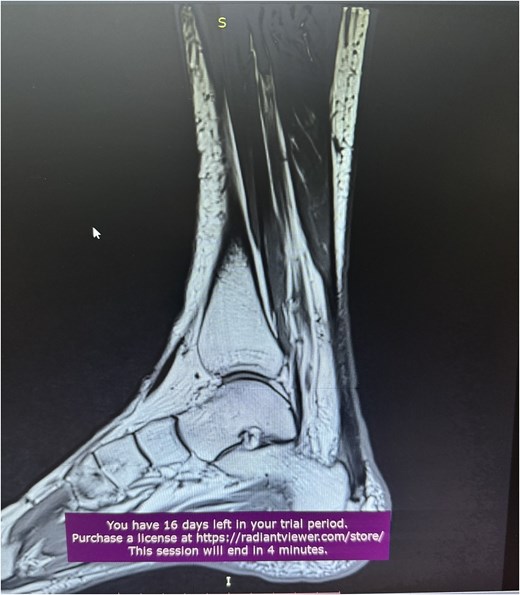

A comprehensive physical examination provided significant insights into the patient’s condition following the Achilles tendon rupture. The Thompson test was particularly noteworthy, showing an absence of plantar flexion upon calf compression, strongly indicating a complete tendon rupture. The examination further revealed a palpable gap in the Achilles tendon and increased passive dorsiflexion. Symptoms included significant weakness, difficulty walking and heel pain. Imaging studies, including X-rays (Fig. 2) and magnetic resonance imaging (MRI) (Fig. 3), confirmed these findings, showing an acute rupture with retracted tendon edges, distinguishing it from chronic condition and suggesting a possible link to the vigorous ultrasound therapy [3].